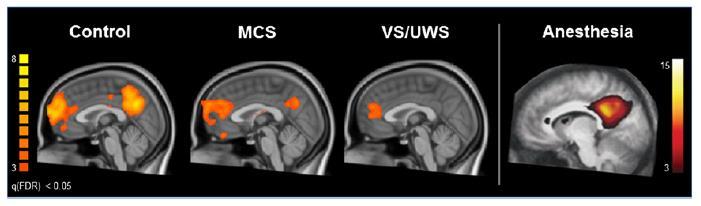

Consciousness is a multifaceted concept that has two major components: awareness of environment and of self (i.e. the content of consciousness) and wakefulness (i.e. the level of consciousness). You need to be awake to be aware (REM-sleep being a notable exception). There are situations in which wakefulness and awareness are dissociated. The most tragic example is the vegetative state.

A TBI can cause problems with consciousness, awareness, alertness, and responsiveness. Generally, there are four abnormal states that can result from a severe TBI:

Vegetative State/Unresponsive wakefulness syndrome (UWS)

A result of widespread damage to the brain, people with UWS are unconscious and unaware of their surroundings.

However, they can have periods of unresponsive alertness and may groan, move, or show reflex responses.

VS is a specific neurobehavioral diagnostic term that indicates complete loss of the ability to interact with the environment despite the capacity for spontaneous or stimulus-induced arousal.

• Behavioral responses consist of reflexive reactions only.

• Sleep/wake cycles may be present on EEG, and subcortical reflexes are partially or fully preserved.

• Vegetative (ie, autonomic) functions may no longer require artificial support.

• No specific neuropathological correlates exist; however, the VS is frequently observed in patients who manifest severe bi-hemispheric pathology with relative preservation of brain stem structures.

1. The patient opens their eyes spontaneously or after external stimulus.

2. Criteria 2, 3, 4, 5, and 6 for the diagnosis of coma are met.

This term should be reserved for use with those patients whose responses are inconsistent but indicative of meaningful interaction with the environment.

The capacity for environmental interaction is evident on observation or is elicitable through testing.

Meaningful responses are characteristically inconsistent and often dependent on external stimulation.

MINIMALLY CONSCIOUSS STATEfull arousal level and inconsistent but reproducible evidence of awareness

MINIMALLY CONSCIOUSS STATE +

evidence of command-following, intelligible verbalization, or intentional communication

VEGETATIVE STATE/UNRESPONSIVE WAKEFULNESS SYNDROME

higher level of arousal without awareness of self or environment